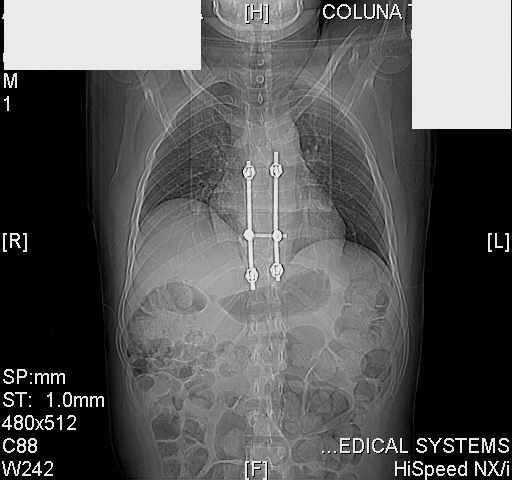

dear all (George?) Got a note this morning requesting an opinion about a patient 25 yrs froma remote area of the country who received this "excellent" stabilization of a fracturedthoracic spine over a year ago.The original neurosurgeon liberated the patient for fullactivities and rehab etc.The rehab doc wants to know what to do. Looks to me like the patientwas screwed pretty good! any offers?

Tom, Harrington rods from a medical museum, with industrial strength screws from a boatbuilder. What are the current symptoms?

Interesting case. Findings on CT: all four pedicle screws have been placed improperly inthat they miss the vertebral bodies. In addition, the screws on the left side are impingingon the decending thoracic aorta. What I do NOT know is the nature of the original injury, orwhether or not that injury has resolved. I would recommend removal of the hardware. I don'tthink it's a good idea to leave those screws where they are. If the original fracture ishealed, nothing else needs to be done.

dear Mark, all the details are not yet available but the patient is coming to see us foradvice. We probably will see him in the early new year. i thought that the 4th picture showedthe screw to enter the aorta? He is a victim of a motor vehicle crash and thoracic vertebralfracture which appears healed. He was posteriorly decompressed and this device inserted. asyou say there isno evidenece that any of the fixation enters the bodies via the pediclesistead they have passed thru and their end are no where near where they ought to be. If I amcorrect (I would prefer not to be) the aortic intima has been breached by the screw. When thetime comes to take the screw out I thought we should have control of the aorta.What do you think?